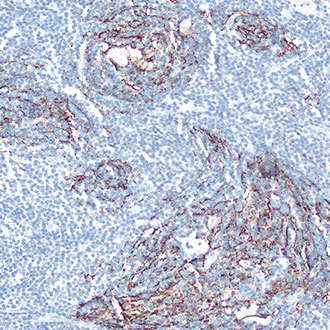

CD21

CD21 -